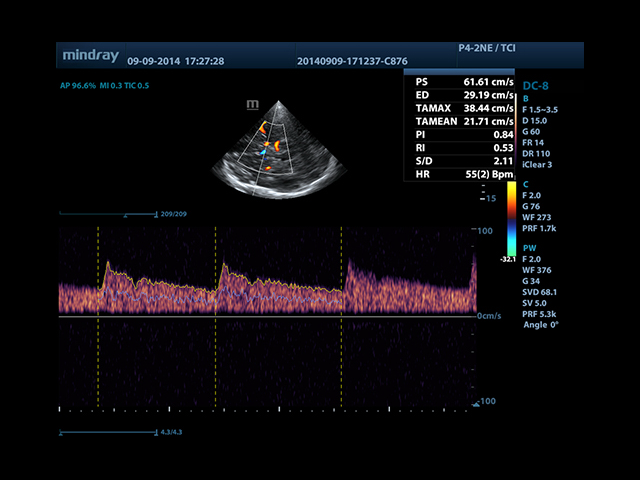

• Smart Doppler - автоматическая подстройка расположения рамки цветового доплера и контрольного объема импульсно-волнового доплера нажатием кнопки.

• Smart Doppler™ - автоматическая подстройка расположения рамки цветового допплера и контрольного объема импульсно-волнового допплера

• TDI (Tissue Doppler imaging, including TDI Color, Power, PW and M mode) - пакет тканевой допплерографии, включая цветное картирование, импульсный тканевой допплер, энергетический тканевой допплер и тканевой М-режим